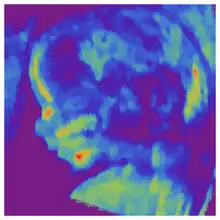

Contents in the cavity of the uterus seen at approximately 5 weeks of gestational age

Artificially colored, showing gestational sac, yolk sac and embryo (measuring 3 mm as the distance between the + signs)